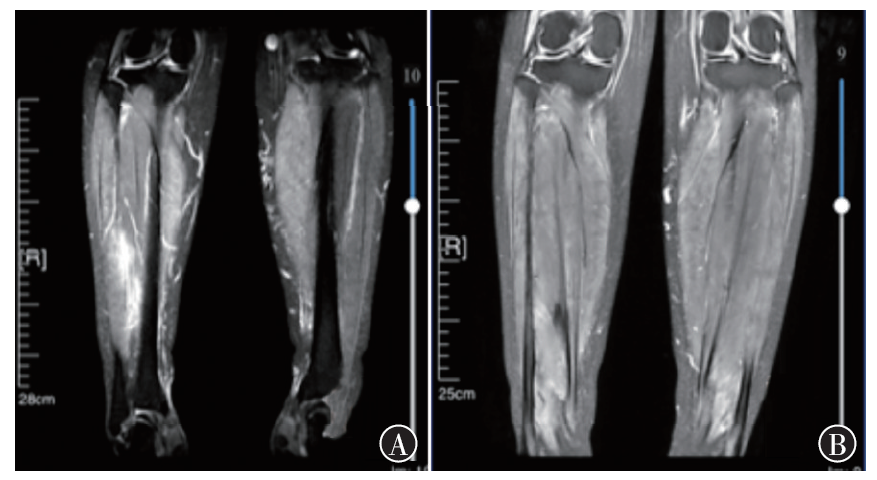

宫颈癌肌间转移不常见,小腿肌间转移尤为罕见。现报道1例宫颈癌小腿肌间转移病例。目前针对远处肌间转移的宫颈癌治疗虽无统一的治疗标准,但仍以多学科会诊为主,争取给患者获得更多的治疗选择和生存机会,使患者获益最大化。